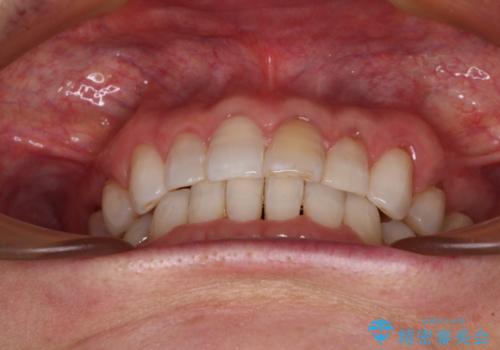

矯正治療の後戻り インビザライン・ライトでの再矯正

- 上下前歯を中心に、以前行った矯正治療の後戻りが気になるとのことで来院された患者様です。

後戻りは軽度であったため、インビザライン・ライトにて治療を行うこととしました。

矯正治療後は、再度後戻りすることを極力回避するために、下顎前歯の舌側を細いワイヤーを用いて保定することとしました。